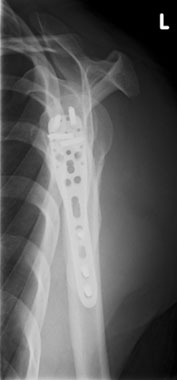

In diesem Fall ist eine winkelstabilen Plattenosteosynthese indiziert. Durch die winkelstabile Schraubenverankerung im Plattenlager und divergierenden Schraubenverlauf, welcher die ganze Breite des Kopffragmentes nutzt, wird eine hohe primäre Stabilität erreicht. Dies ermöglicht eine frühfunktionelle Übungsstabilität bei gleichzeitiger

Schmerzreduktion. |